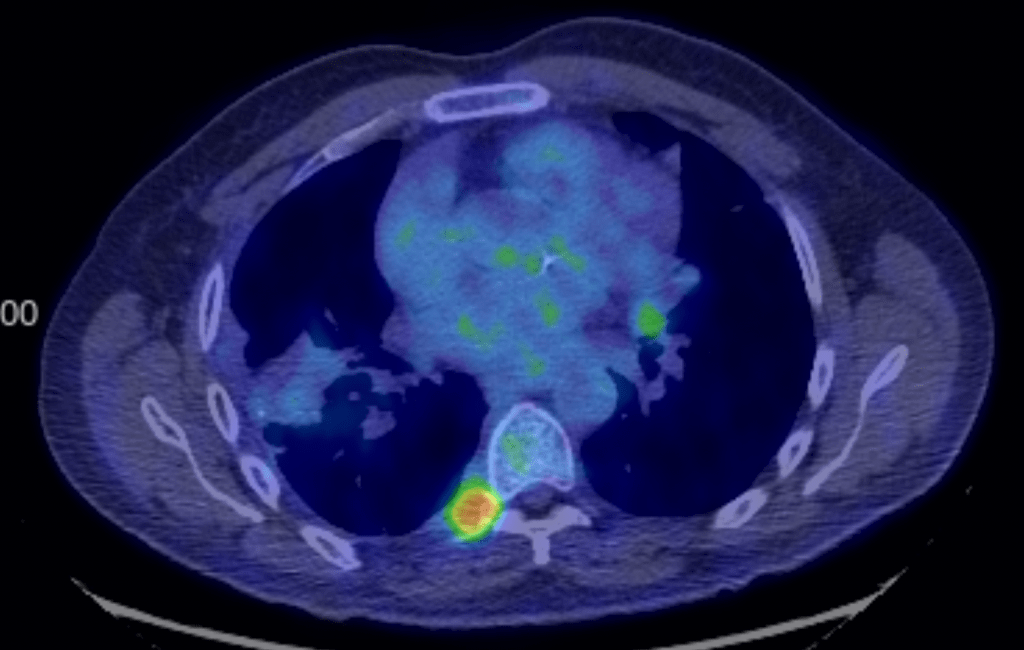

Update: My March 5th PET scan showed that while most of my tumors are completely gone, I have a few persistent tumors that will need to be addressed. I have 2 prominent ones, and a few minor ones. We met with my chemo oncologist and we agreed that the current approach isn’t quite working and we need a different approach. We decided to get a biopsy on the lung tumor which is relatively accessible. So just yesterday, we went to the hospital for a lung biopsy, performed by my pulmonologist. The procedure went well. He’ll send off the biopsy for Next Generation Sequencing which will give us information on the genetics of the tumor. This should give us good information about what chemo or immunotherapy treatments to use next. We’ll have that information back in a few weeks.

Then we spoke to my radiation oncologist just today. He’s mostly concerned about the tumor near the spine. The good news is that he thinks it’s far enough away from my spinal cord that he can treat it without doing any damage to my nervous system, which is great. That will probably happen in about 3 weeks. We’ve had success with radiation in the past, and we’re encouraged that he can treat that area.